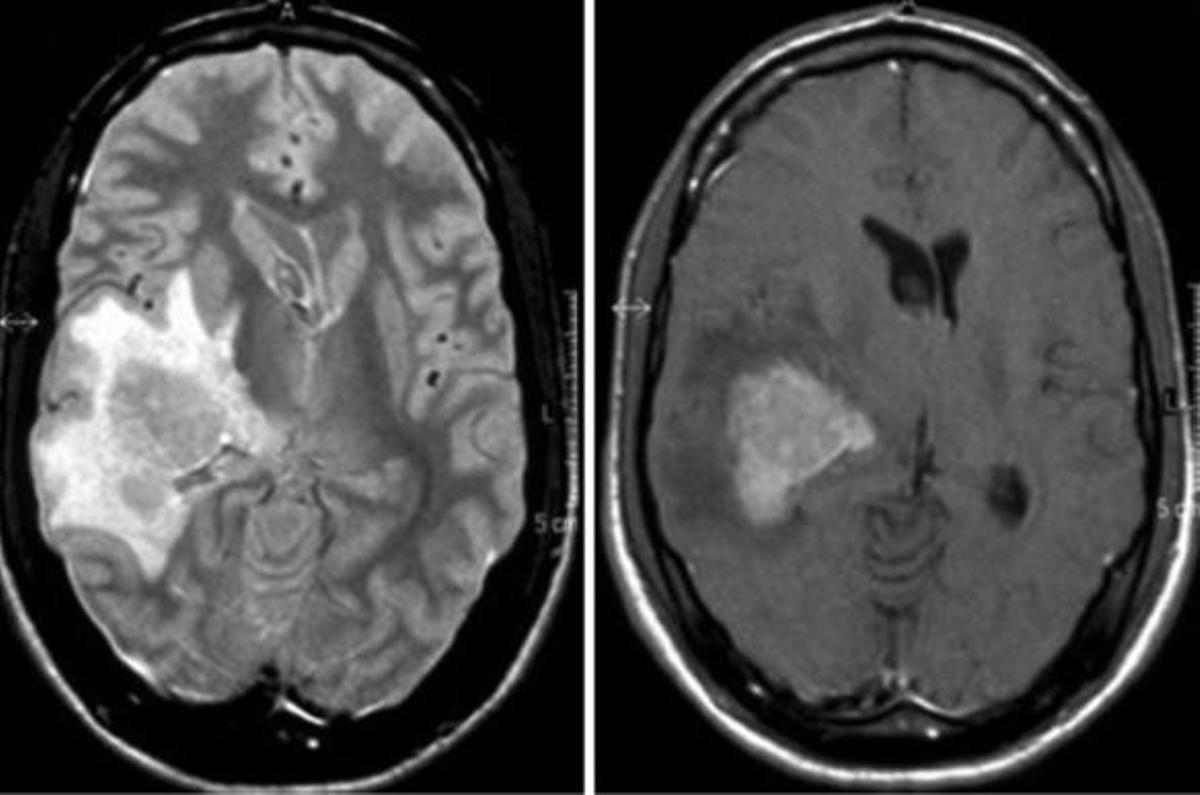

Limfoma cerebral, en una imatge d'arxiu / EPE